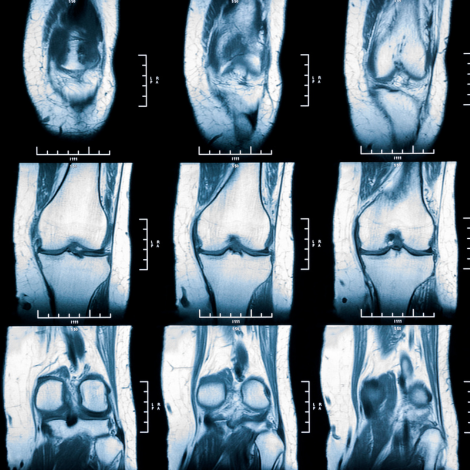

Knee MRI

An MRI of the knee helps find problems such as damage to the ligaments and cartilage around the knee. The MRI also can look for the cause of unexplained knee pain, or infections in or around the knee.